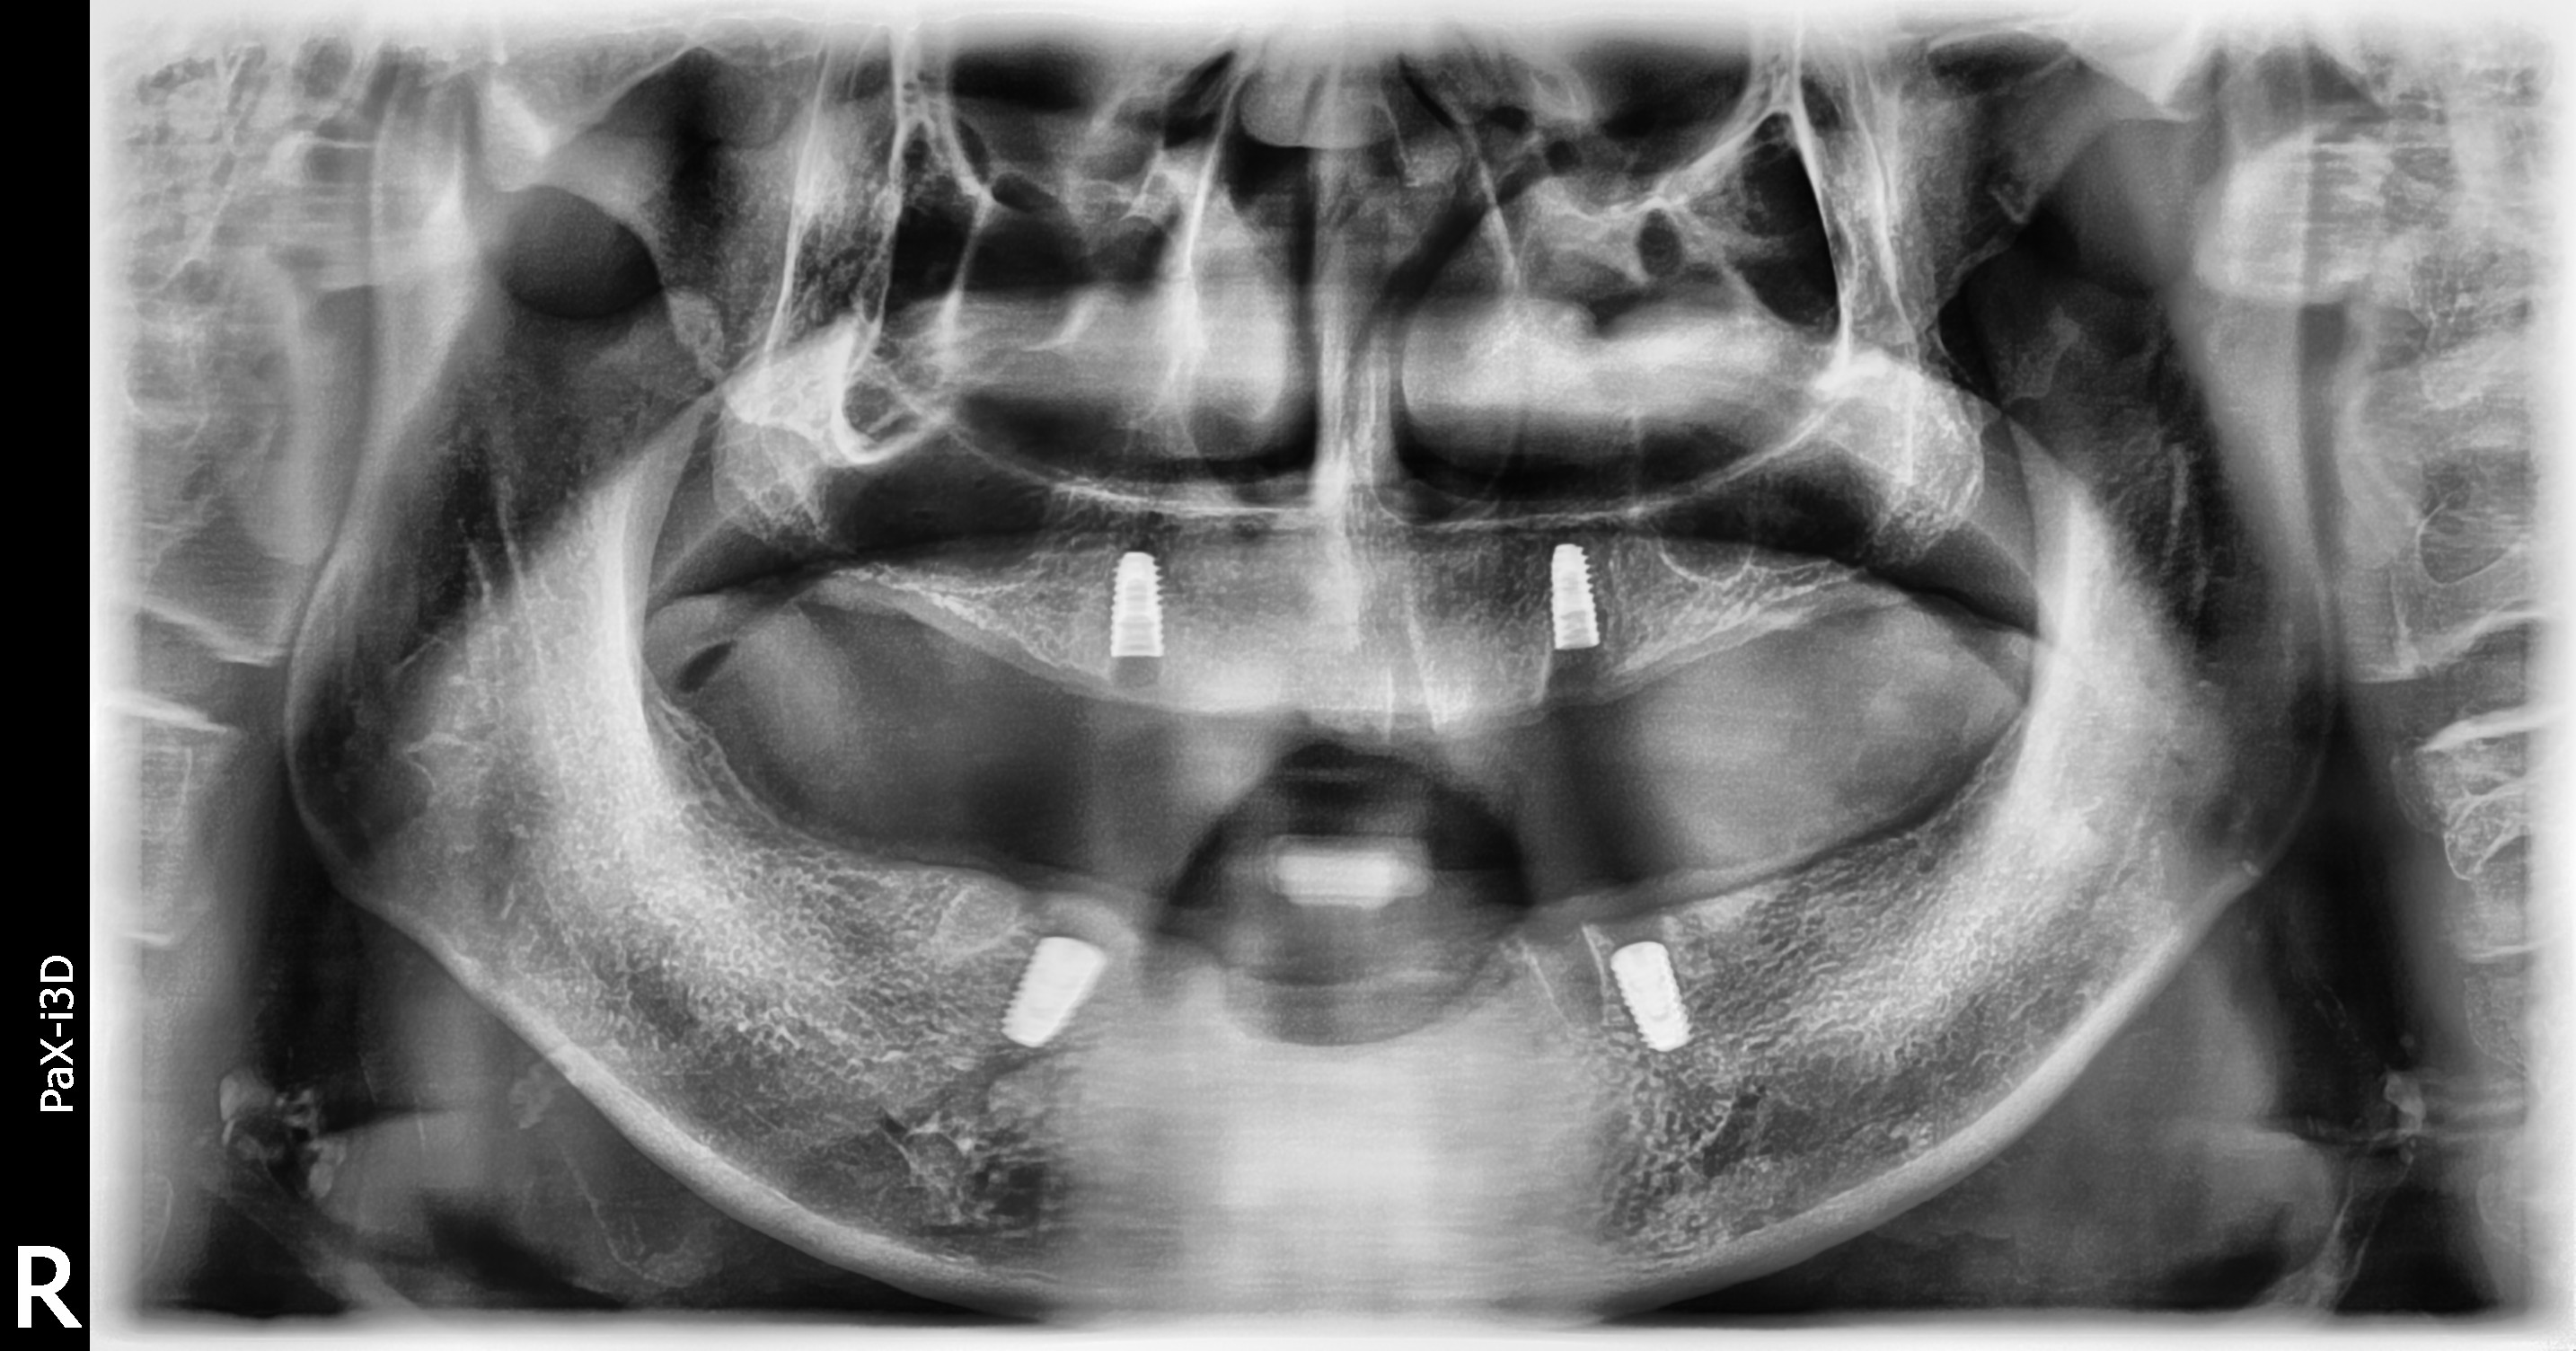

BEFOREAFTERBEFOREAFTER(식립)AFTER(착용)

임플란트 틀니